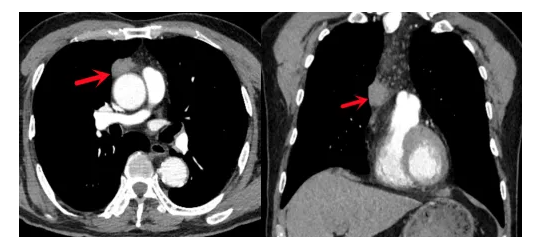

患者刘先生此前因前纵隔发现约3公分肿物前来就诊。CT显示肿物紧贴心脏大血管,不排除恶性可能,具备明确手术指征。考虑到患者对传统开胸手术存在顾虑,李卫国副主任医师耐心解释纵隔肿物远期危害及手术必要性,并详细介绍“免管”胸腔镜剑突下切除方案。该术式创伤小、疼痛轻,符合快速康复理念,患者及家属同意手术。